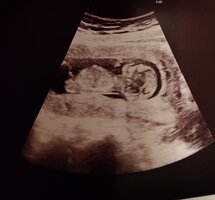

Nub-teorian mukaan sukupuolen voi määrittää jo nt-ultrassa genitaalikyhmyn asennon perusteella. Voit lukea aiheesta lisää täältä.

Kiinnostaako teitä sukupuolen määrittäminen kyseisen teorian avulla? Katsotteko ultrakuvia sillä silmällä?